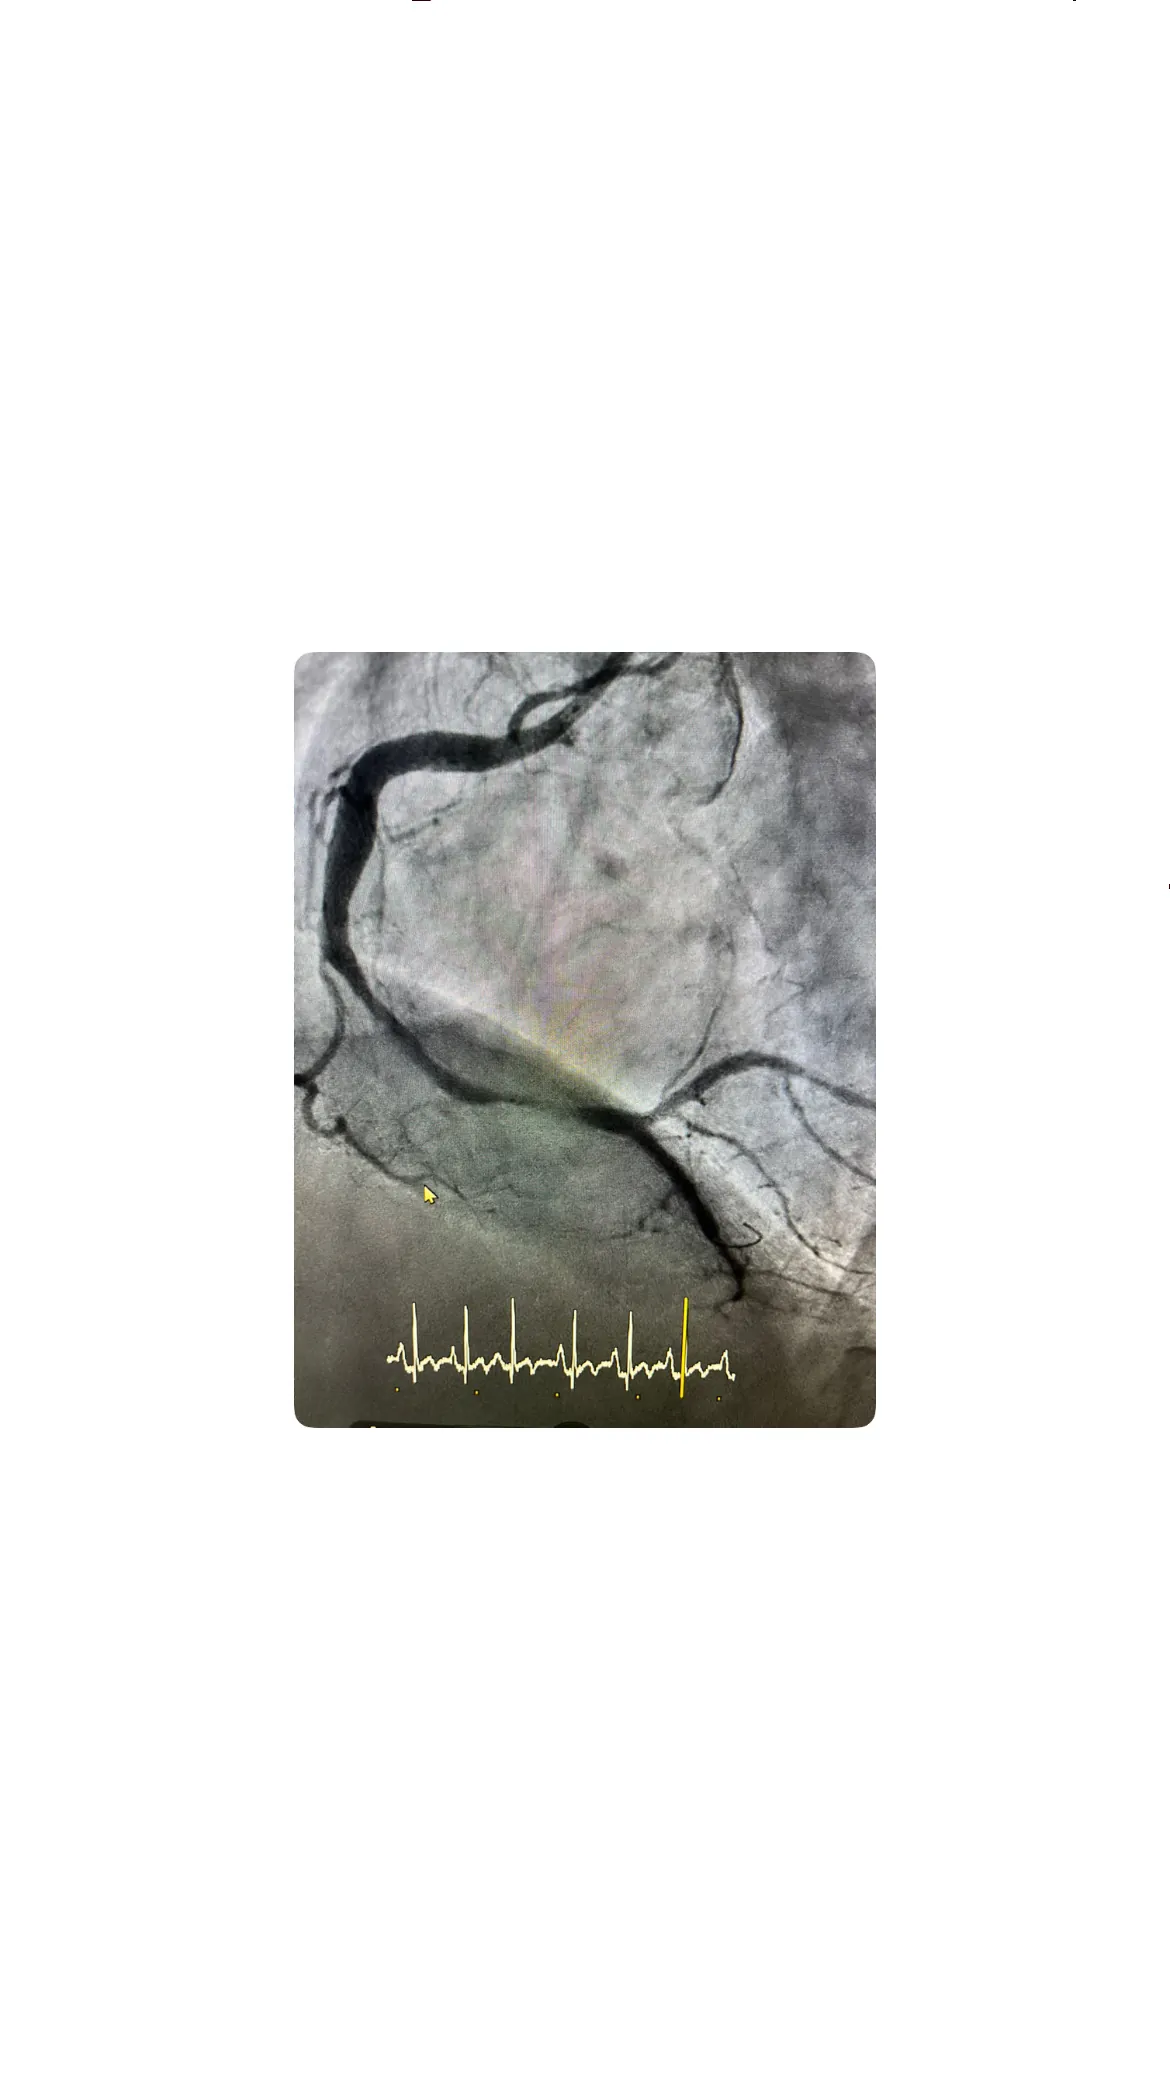

Durante el cateterismo cardíaco, el objetivo principal es identificar la arteria responsable del infarto y restaurar el flujo coronario lo antes posible. En este caso, al avanzar con el catéter y contrastar las arterias coronarias, se observa que la arteria relacionada con el territorio inferior se encuentra ocluida, lo que explica la elevación del ST en D2, D3 y aVF. Este hallazgo confirma de forma anatómica el diagnóstico de un SCACEST inferior y orienta la estrategia de revascularización hacia la apertura mecánica de la lesión mediante angioplastia.

La estrategia elegida combina varias técnicas: paso de guía a través de la oclusión, aspiración del trombo y predilatación con balón antes de la implantación del stent. Esta secuencia permite primero atravesar la lesión, luego reducir la carga trombótica y finalmente preparar la arteria para recibir el stent de forma óptima. Todo el procedimiento se desarrolla con la paciente estable, sin complicaciones hemodinámicas relevantes, lo que contribuye a que se considere un cateterismo sencillo, o como se describe coloquialmente, un cateterismo Killip I, es decir, no complicado.

El acceso radial derecho se realiza tras confirmar un buen pulso y preparar el campo estéril, introduciendo el introductor de forma cuidadosa para evitar espasmos o complicaciones locales. Una vez dentro del sistema arterial, se avanza el catéter hasta las coronarias y se inyecta contraste para visualizar el árbol coronario, observándose claramente la oclusión en la arteria responsable del territorio inferior. Este hallazgo explica tanto el dolor torácico como la elevación del ST en las derivaciones inferiores, y marca el punto de partida para la intervención terapéutica dirigida a restaurar el flujo.

Recuperación del flujo y normalización del ST en el ECG

Con la aspiración del trombo y la predilatación con balón, la arteria comienza a recuperar el flujo de manera visible en las imágenes angiográficas, pasando de una oclusión completa a un flujo restablecido. Esta mejoría anatómica se traduce de forma casi inmediata en el electrocardiograma, donde la elevación del ST en las derivaciones inferiores empieza a desaparecer, indicando que el miocardio vuelve a recibir sangre oxigenada. La correlación entre la apertura de la arteria y la normalización del ST es uno de los momentos clave del procedimiento, ya que confirma que la estrategia de revascularización está siendo efectiva y que se está limitando el tamaño del infarto.